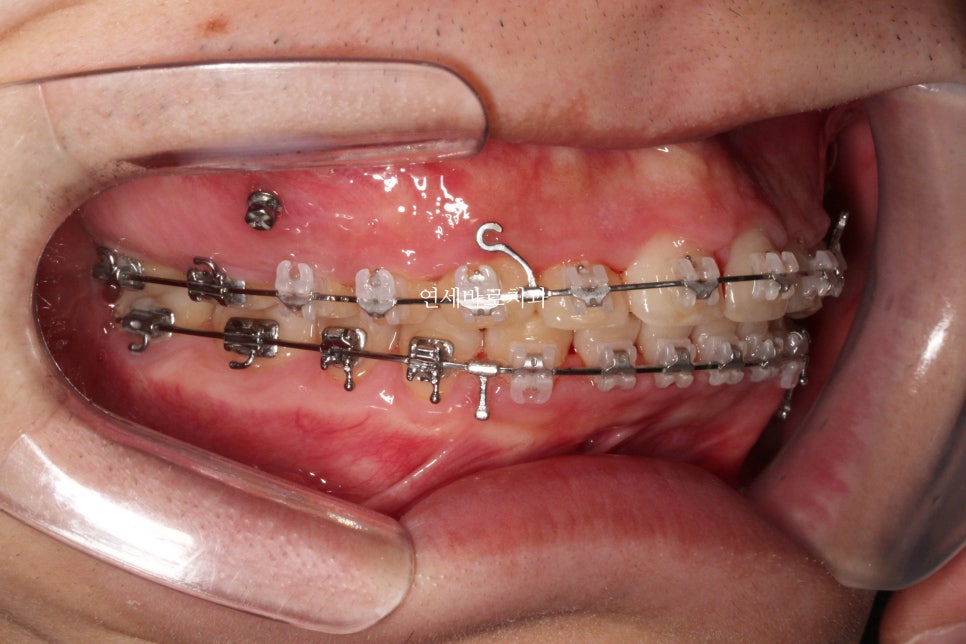

어금니 관계를 보면 1:1 로 만나던 치아가 사이사이 지그재그 들어가는 것이 보이죠?

약 5mm정도 후방이동 된 것으로 보입니다.

워낙 짧은 치관 길이와 골격형태가 교정치료를 하기 어려운 상황이긴 했지만,

환자분이 내원간격도 잘 지켜주시고, 오랜기간 변함없이 잘 참아주셔서 좋은 결과를 얻을 수 있었던 것으로 생각합니다.

2019.8.30.에 저희 병원에 처음 오셨고 1달뒤 치료 시작

2022.9.27.에 치료 끝나셨으니 약 3년간 치료했습니다.

3년 중 약 2년반은 당기기만 했고, 오셔서 고무줄만 갈아끼고 가셨습니다.